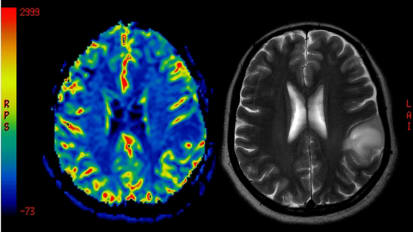

Leading the fight against brain metastases, Baptist Health Miami Cancer Institute hit a new milestone recently. The center treated its 1000th patient using Gamma Knife radiosurgery, an incisionless radiation therapy that precisely targets a tumor, importantly minimizing damage to otherwise healthy brain tissue.New Class of Drugs Show Promise in Treating Recurrent Cervical Cancer